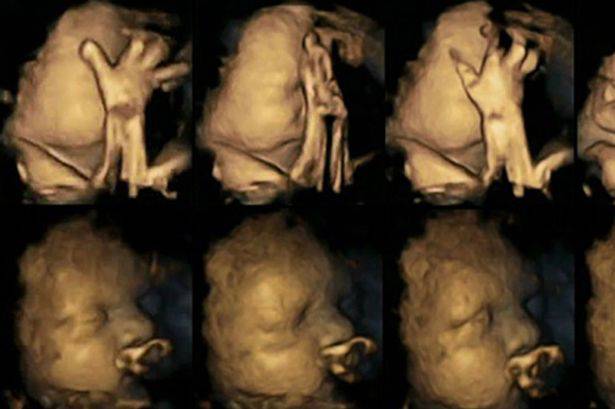

Una ricerca, condotta dalla Durham University e dalla Lancaster University, e pubblicata sulla rivista Acta Paediatrica, ha cercato di mostrare gli effetti del fumo sui bambini direttamente nel grembo materno, attraverso l’osservazione dei piccoli movimenti sui loro volti. Per produrre le immagini sono state utilizzate ecografie 4D.

La dottoressa Nadja Reissland, del Dipartimento di Psicologia della Durham University, ha studiato le immagini ed ha registrato migliaia di piccoli movimenti, monitorando 20 mamme presso l’University James Cook Hospital a Middlesbrough. Di queste 20 donne, 4 fumavano una media di 14 sigarette al giorno. Dopo aver studiato le scansioni a 24, 28, 32 e 36 settimane, la dottoressa ha rilevato che i feti le cui madri fumavano, mostravano tassi significativamente più alti di movimento della bocca e dei “toccamenti” rispetto ai tassi dei feti di madri non fumatrici. Questo perché di solito i feti verso la fine della gravidanza riescono ad ottenere un maggior controllo dei movimenti e riducono quindi il numero di volte in cui si toccano o muovono la bocca.